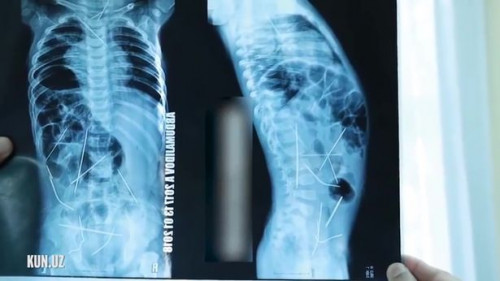

Bé trai 11 tháng tuổi ở Ferghana, Uzbekista sốt cao, tiểu tiện khó được đưa vào viện cấp cứu. Khi chụp X-quang, các bác sĩ không thể ngờ vào mắt mình khi phát hiện trong bụng bệnh nhi có tới 16 cây kim khâu.

Theo thông tin trên trang Mirror, các bác sĩ của một bệnh viện ở vùng Ferghana, Uzbekistan đã phẫu thuật thành công lấy ra 13/16 cây kim khâu trong bụng bé trai 11 tháng tuổi

Sau khi chụp X-quang, các bác sĩ phát hiện trong bụng bệnh nhi có 16 cây kim khâu.

Theo đó, bé trai được mẹ đưa tới bệnh viện trong tình trạng sốt cao và gặp khó khăn trong việc tiểu tiện. Sau khi chụp X-quang, các bác sĩ phát hiện trong bụng bệnh nhi có 16 cây kim khâu.

Em bé sau đó được chuyển vào phòng phẫu thuật trung tâm cấp cứu ở thành phố Tashkent, và được tiến hành ca mổ cấp cứu gấp trong suốt 9 tiếng. Tuy nhiên, ca phẫu thuật lần này các bác sĩ mới chỉ lấy ra 13 cây kim, bao gồm ba cây kim ở ngực, 9 cây ở bụng và một cây ở cổ. Cậu bé 11 tháng tuổi sẽ phải trải qua ca phẫu thuật thứ 2 để lấy nốt 3 cây kim khâu còn lại ra ngoài.

Ban đầu, các bác sĩ nghi ngờ bé bị viêm phổi, tuy nhiên, kết quả X-quang cho thấy những chiếc kim đang mắc kẹt trong tim, cổ, cột sống và bàng quang em.